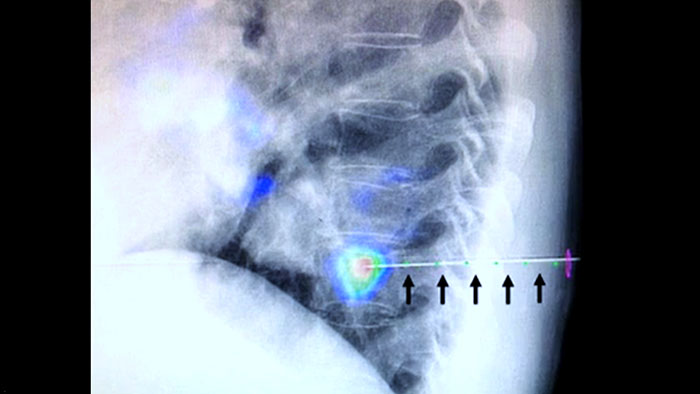

Технология XperGuide обеспечивает точный визуальный контроль при ведении иглы к исследуемой области в режиме реального времени, накладывая изображения предварительно запланированной траектории на рентгеноскопические изображения3.